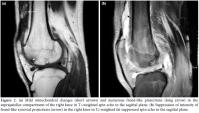

X-rays of the knees were normal except for mild degenerative changes. Sonographic examinations of the knees were performed by the Logiq 9 ultrasound imager (GE Medical Systems, Milwaukee, Wis) with a high frequency linear array probe. These revealed globular and villous hyperechoic structures projecting into the suprapatellar effusion in the right knee. There were focal areas of hyperechogenicity suggesting fatty deposition (Figure 1). Magnetic resonance imaging was performed using a 1.5-T MR unit (Symphony Vision, Siemens Medical Systems) with an extremity coil for knee studies. The sequence included T1- and T2-weighted spin echo, T1-weighted gradient echo, and T2-weighted fat-suppressed spin echo in the axial, coronal, and sagittal planes.

Magnetic resonance imaging revealed a large effusion and numerous frond-like projections which were prominent in the suprapatellar compartment of right knee. The intensity of these frond-like synovial projections, which were suppressed in fatsaturated sequences, was similar to the intensity of fat (Figures 2a, b). An effusion and a mass-like lesion were also detected in the popliteal bursa of the right knee. (Figures 3a, b) In addition, mild osteochondral changes occurred in both knees which were more pronouced on the right side (Figure 2a). Suprapatellar effusion was also detected in the left knee. No meniscal or ligament pathology was detected in either knee.